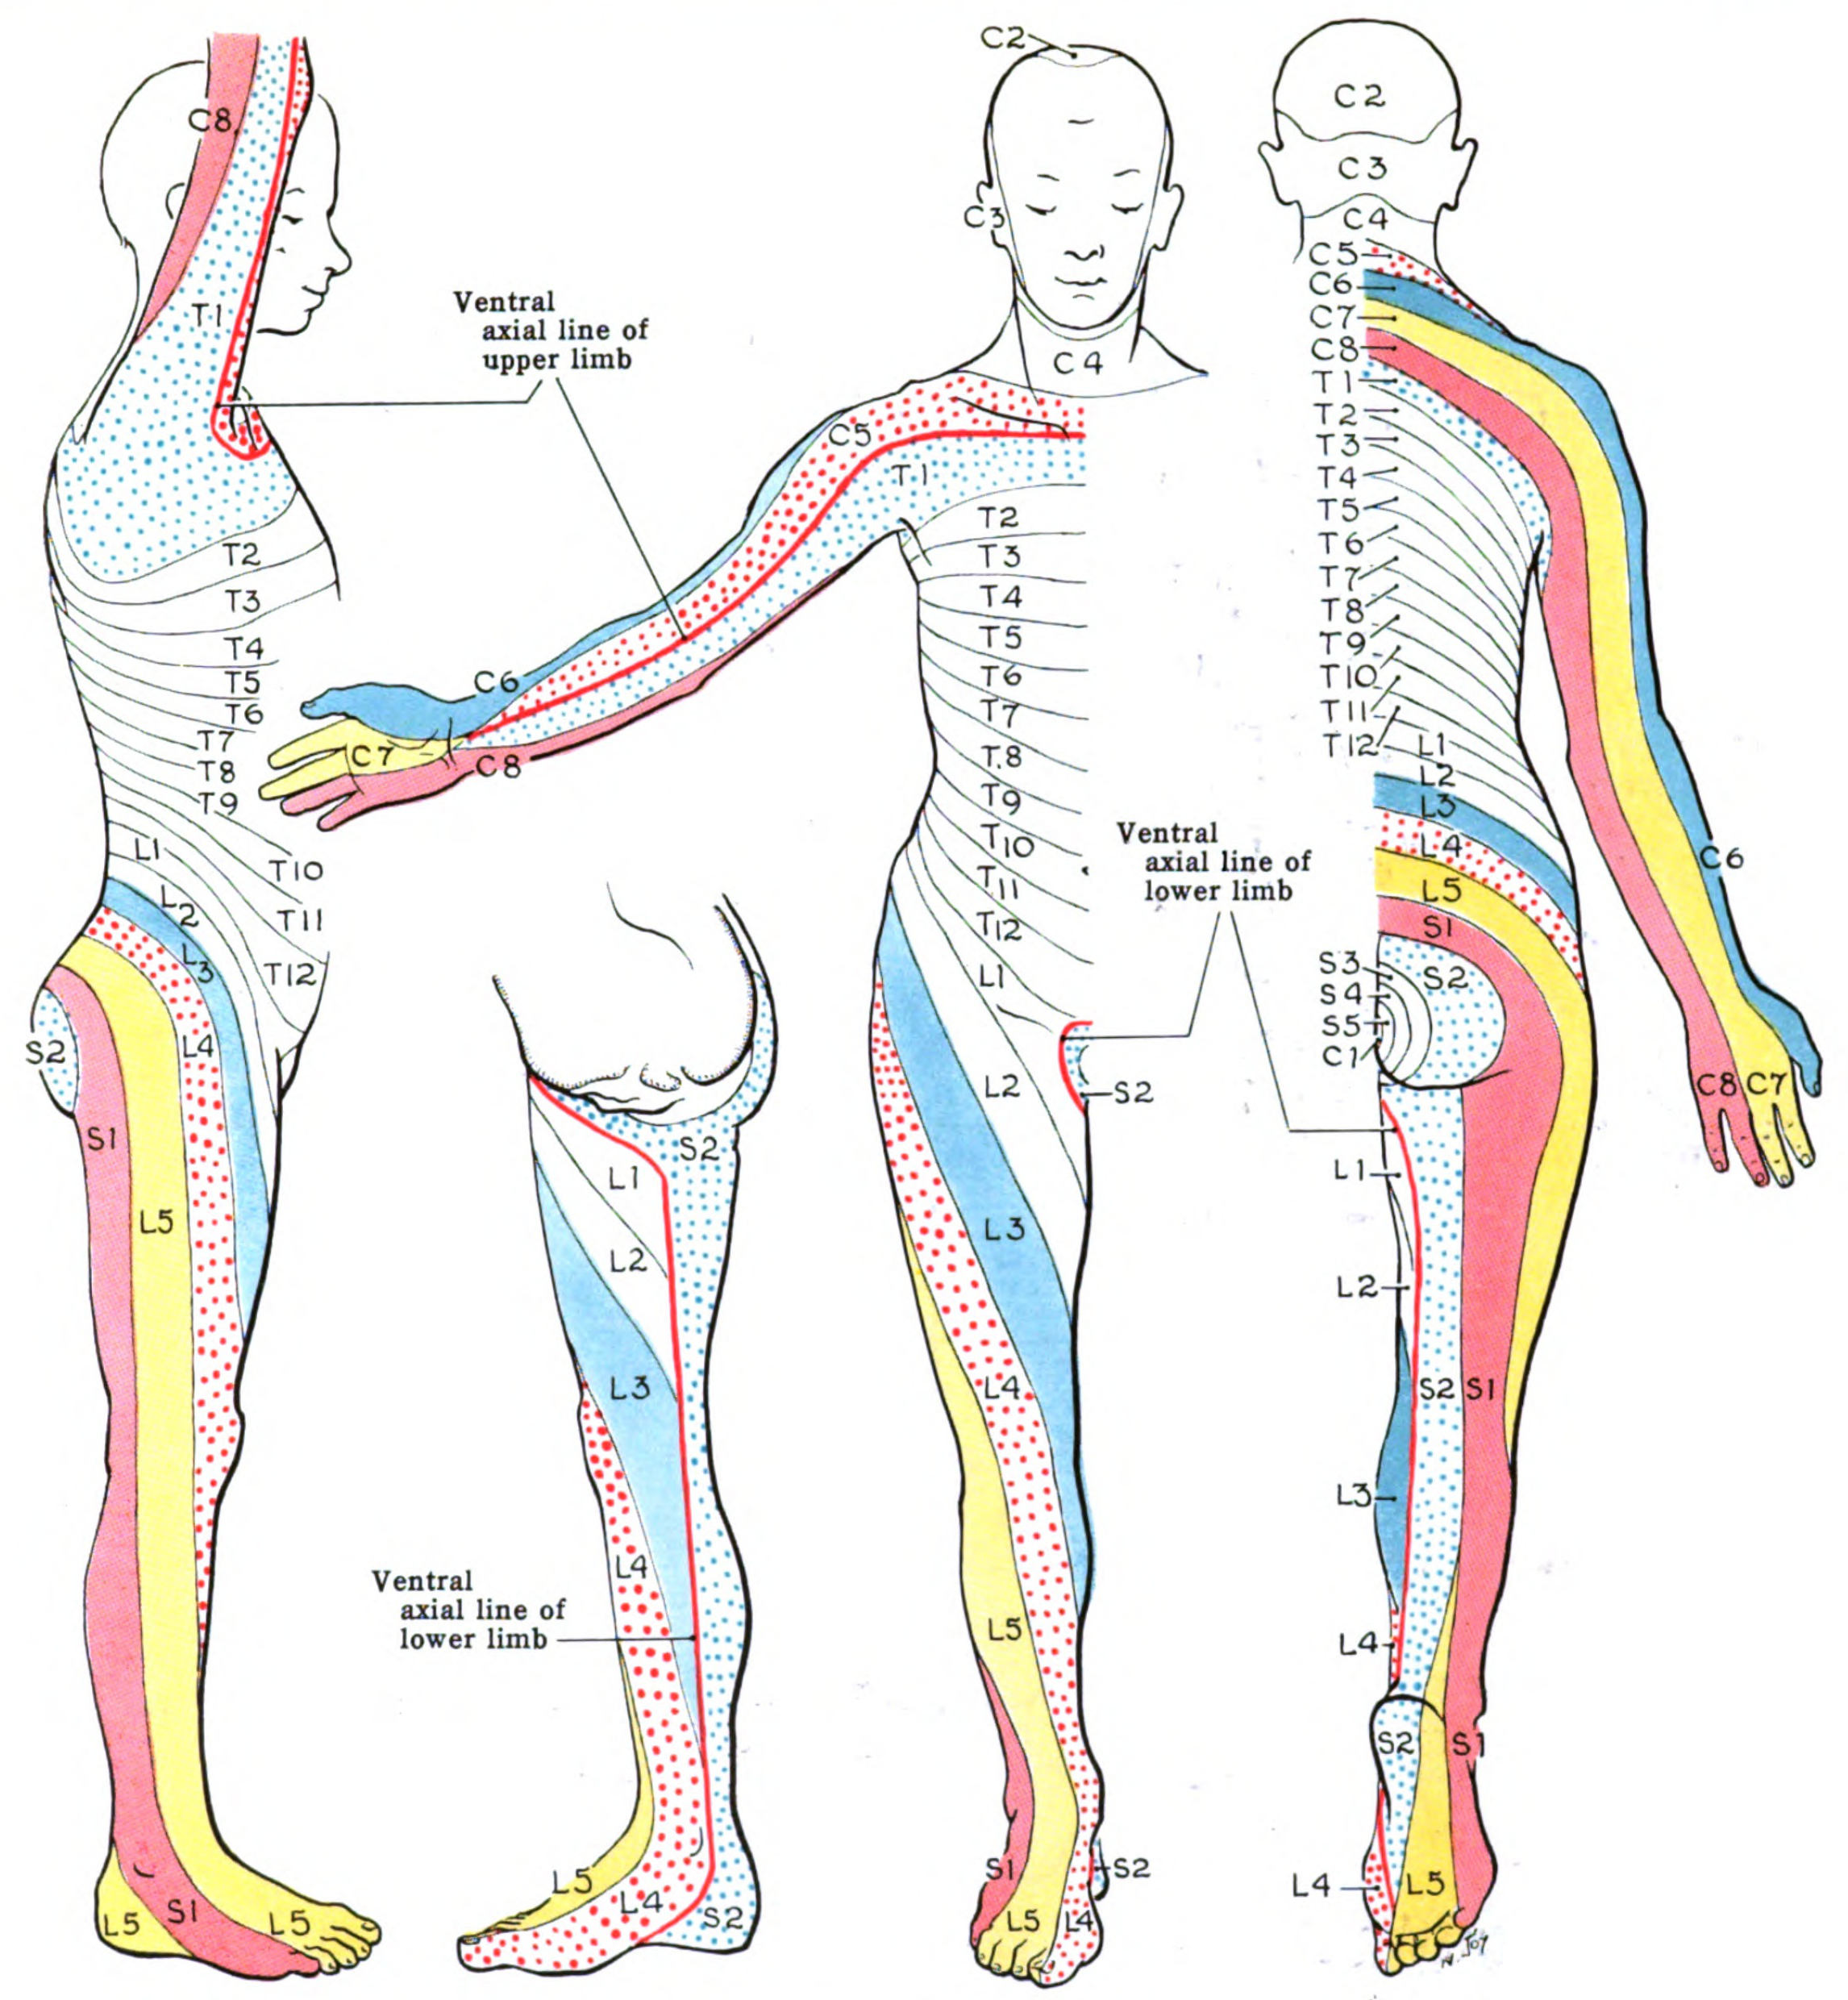

Dermatomal segments of the body

Note:

image is public domain. Grant, John Charles Boileau - An atlas of anatomy, / by regions 1962 https://en.wikipedia.org/wiki/Dermatome_(anatomy)#/media/File:Grant_1962_663.png